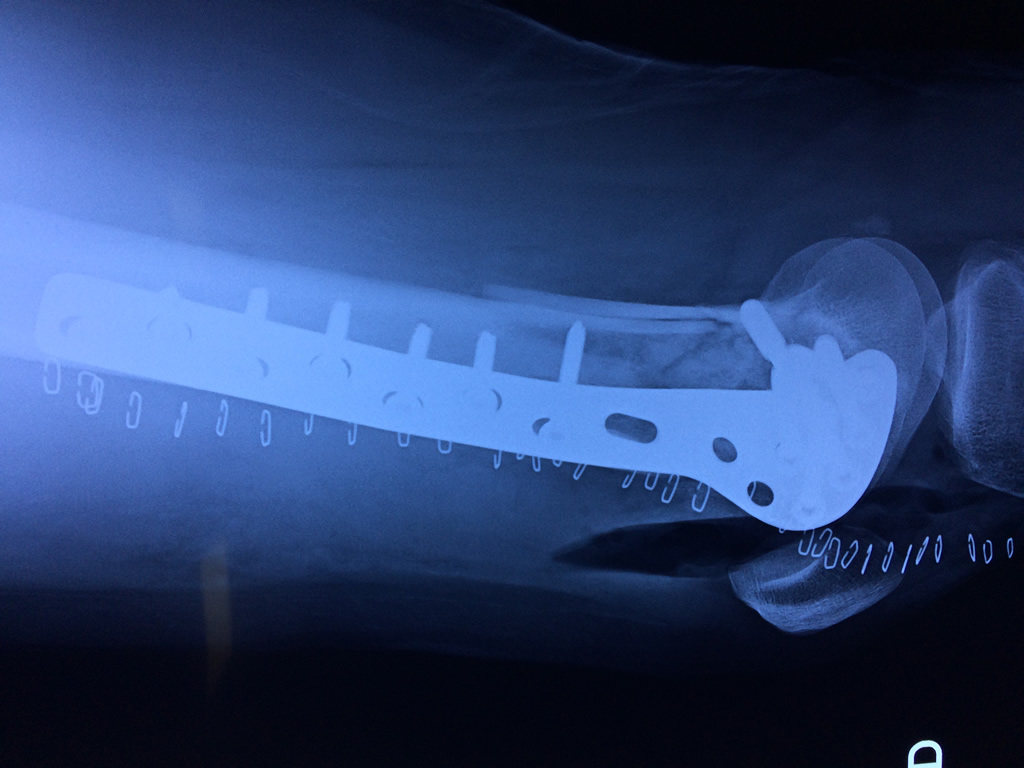

Calcaneo - Fémur

El fémur es el hueso del muslo, el segundo segmento del miembro inferior. Es el hueso más largo, fuerte y voluminoso del cuerpo humano.